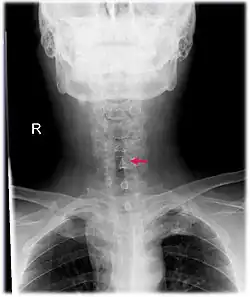

| Neck AP x-ray of patient with post-intubation subglottic stenosis, as shown by the narrowing in the tracheal lumen marked by the arrow. | |

Subglottic stenosis is a congenital or acquired narrowing of the subglottic airway.[1] It can be congenital, acquired, iatrogenic, or very rarely, idiopathic. It is defined as the narrowing of the portion of the airway that lies between the vocal cords and the lower part of the cricoid cartilage. In a normal infant, the subglottic airway is 4.5-5.5 millimeters wide, while in a premature infant, the normal width is 3.5 millimeters. Subglottic stenosis is defined as a diameter of under 4 millimeters in an infant. Acquired cases are more common than congenital cases due to prolonged intubation being introduced in the 1960s.[2] It is most frequently caused by certain medical procedures or external trauma, although infections and systemic or autoimmune diseases can also cause it.

CT scans and MRI (magnetic resonance imaging) can help in diagnosis. X-rays can determine the location and size of the narrowed airway portion. Optical coherence tomography (OCT) can help observe the progression of the injury. Esophageal pH monitoring can help detect any acid reflux, which can worsen the condition. A laryngoscopy or an endoscope can be inserted and used to see the vocal cords, airway, and esophagus/trachea. Spirometry is a useful way to measure respiratory function. People affected by subglottic stenosis have a FEV1 of over 10.[2]